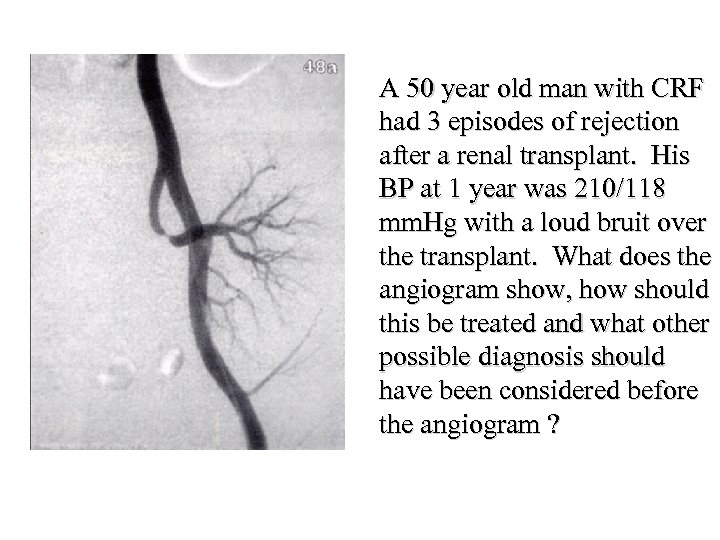

Carpe Diem! and good luck

Carpe Diem! and good luck

4. A 29 -year-old woman presents with weakness and is found to have a serum potassium of 2. 2 mmol/l and p. H 7. 1. Which of the following would be most suggestive of proximal renal tubular acidosis (RTA type 2)? • • • A B C D E Renal calculi Osteomalacia Serum bicarbonate 8 mmol/l Urinary p. H 6. 5 History of Sjogren’s syndrome

4. A 29 -year-old woman presents with weakness and is found to have a serum potassium of 2. 2 mmol/l and p. H 7. 1. Which of the following would be most suggestive of proximal renal tubular acidosis (RTA type 2)? • • • A B C D E Renal calculi Osteomalacia Serum bicarbonate 8 mmol/l Urinary p. H 6. 5 History of Sjogren’s syndrome

4. A 29 -year-old woman presents with weakness and is found to have a serum potassium of 2. 2 mmol/l and p. H 7. 1. Which of the following would be most suggestive of proximal renal tubular acidosis (RTA type 2)? • • • A B C D E Renal calculi Osteomalacia Serum bicarbonate 8 mmol/l Urinary p. H 6. 5 History of Sjogren’s syndrome

4. A 29 -year-old woman presents with weakness and is found to have a serum potassium of 2. 2 mmol/l and p. H 7. 1. Which of the following would be most suggestive of proximal renal tubular acidosis (RTA type 2)? • • • A B C D E Renal calculi Osteomalacia Serum bicarbonate 8 mmol/l Urinary p. H 6. 5 History of Sjogren’s syndrome

How do kidneys regulate acid base balance?

How do kidneys regulate acid base balance?

Bicarbonate is freely filtered by glomerulus Then nearly all reabsorbed by PCT H+ excreted at cortical collecting duct to maintain normal p. H

Bicarbonate is freely filtered by glomerulus Then nearly all reabsorbed by PCT H+ excreted at cortical collecting duct to maintain normal p. H

What can go wrong? Type 2 - Proximal RTA due to failure of bicarbonate reabsorption (uncommon in adults) Type 1 - Distal RTA due to failure of acid secretion (common) Type 3 - Poorly characterised mix of types 1 and 2 (vanishingly rare) Type 4 - Hyporeninaemic hypoaldosteronism causing acidosis and hyperkalaemia (common)

What can go wrong? Type 2 - Proximal RTA due to failure of bicarbonate reabsorption (uncommon in adults) Type 1 - Distal RTA due to failure of acid secretion (common) Type 3 - Poorly characterised mix of types 1 and 2 (vanishingly rare) Type 4 - Hyporeninaemic hypoaldosteronism causing acidosis and hyperkalaemia (common)

Renal tubular acidosis • Distal - type 1 • Proximal - type 2 • rare Frequency • common Mechanism • failure to excrete H+ • failure to reabsorb bicarbonate • 1 y or 2 y to cystinosis, • 1 y or 2 y to SLE, Causes wilsons, myeloma, sjogrens, PBC, sjogrens - often assoc CAH, urinary with failure to reabsorb obstruction, PO 4, AA, glucose, urate medullary sponge, (fanconi) lithium

Renal tubular acidosis • Distal - type 1 • Proximal - type 2 • rare Frequency • common Mechanism • failure to excrete H+ • failure to reabsorb bicarbonate • 1 y or 2 y to cystinosis, • 1 y or 2 y to SLE, Causes wilsons, myeloma, sjogrens, PBC, sjogrens - often assoc CAH, urinary with failure to reabsorb obstruction, PO 4, AA, glucose, urate medullary sponge, (fanconi) lithium

Renal tubular acidosis • Distal - type 1 Urine p. H • • Serum bic • Serum K Complications • Therapy p. H > 5. 5 often < 10 mmol/l usually low nephrocalcinosis, stones • low dose bicarbonate, K supps, citrate to stop Ca-PO 4 deposition if stone former

Renal tubular acidosis • Distal - type 1 Urine p. H • • Serum bic • Serum K Complications • Therapy p. H > 5. 5 often < 10 mmol/l usually low nephrocalcinosis, stones • low dose bicarbonate, K supps, citrate to stop Ca-PO 4 deposition if stone former

Renal tubular acidosis • Distal - type 1 Urine p. H • • Serum bic • Serum K Complications • Therapy • Proximal - type 2 p. H > 5. 5 • often < 10 mmol/l • usually low • nephrocalcinosis, • stones • low dose bicarbonate, • K supps, citrate to stop Ca-PO 4 deposition if stone former Variable* 14 -20 mmol/l* normal or low osteomalacia, rickets (not calcinosis or stones) high dose bicarbonate *when serum bicarb drops below a threshold level in type 2 RTA, the tubules start reabsorbing bicarbonate which means serum bic can be higher and urine p. H lower than in type 1 - known as the “threshold effect”